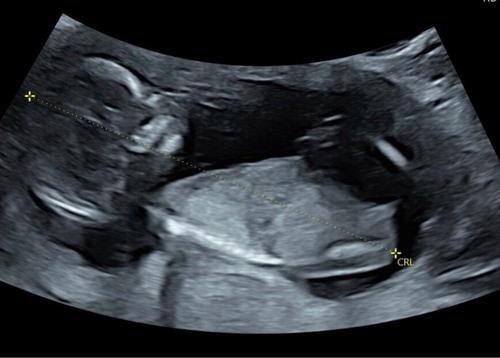

Deel hem hier nog een keer omdat er net een nieuw topic is geopend. 🩷 of 🩵 ?

Deel hem hier nog een keer omdat er net een nieuw topic is geopend. 🩷 of � ...

Ik denk een meisje.